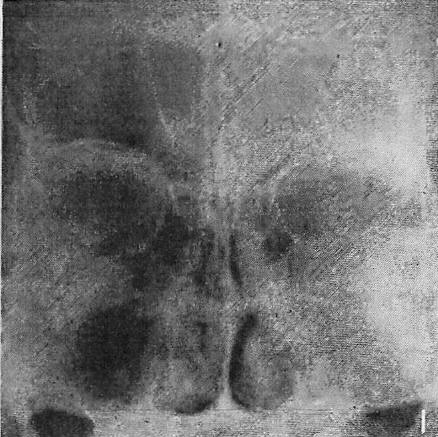

図1. X線写真が脳疾患の診断に役だった史上初の症例.後頭部に銃弾が認められる[2].

当初,頭蓋内病変における頭蓋X線写真の有用性は,金属異物の診断に限られた.1896年9月にスウェーデンの放射線科医Thor Stenbeck*は,後頭部の銃弾をX線写真で診断し,その後脳外科医が摘出に成功した.頭蓋X線撮影が脳疾患の診断治療に役だったおそらく初の報告例である[2](図1,2).